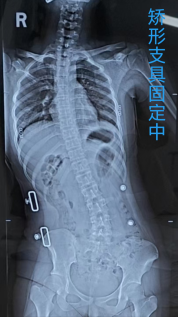

“戴了两个月脊柱侧弯矫形支具,腰没好反而更疼,连上课都得弯腰走!”15岁的小怡(化名)说起此前的经历,满是委屈。原本该活力满满的花季,她却因腰痛在外院被诊断为 “青少年脊柱侧弯”,2个月来每日佩戴矫形支具治疗,不仅侧弯没好转,疼痛反而加重,最后只能佝偻着身子挪动,课堂上坐不住、课后跑不动,正常学习生活全“垮”了。

焦急的家人带着小怡转诊至我院脊柱外科。副主任医师魏林文仔细查体后,发现事情没那么简单——小怡的“侧弯”更可能是疼痛引发的姿势变形。入院完善检查后,真相浮出水面:真正的病因是腰椎间盘突出,突出的髓核已严重压迫神经,而非单纯的脊柱侧弯,因此矫形支具治疗无效。

术后当天,小怡就能挺直腰板,再也不用佩戴笨重的矫形支具。出院时,她和家人特意送来锦旗,小怡踏着欢脱的步伐走出医院,终于能重返校园正常上课。